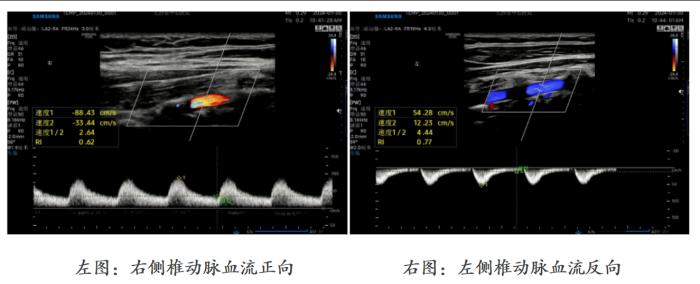

李玲表示,头晕并伴有左上肢无力、发凉的症状已出现近一年时间,她曾尝试多种理疗方法,但症状始终未见好转。近日,李玲到香港马会app 健康管理中心做体检,超声室医生胡婷发现她左侧椎动脉血流完全反向,同时左侧锁骨下动脉开口处存在狭窄。出于职业警觉性,胡婷医生立即带李玲去内科诊室测量了双臂血压,发现其左臂血压(106/65mmHg)显著低于右臂(126/75mmHg),差值超过20mmHg。结合经颅多普勒超声结果,高度怀疑她患上“锁骨下动脉盗血综合征”。李玲随即被转入神经内科,经脑血管造影等检查明确诊断后,接受了左侧锁骨下动脉球囊扩张术+左侧锁骨下动脉支架植入术,术后头晕症状已大幅改善。